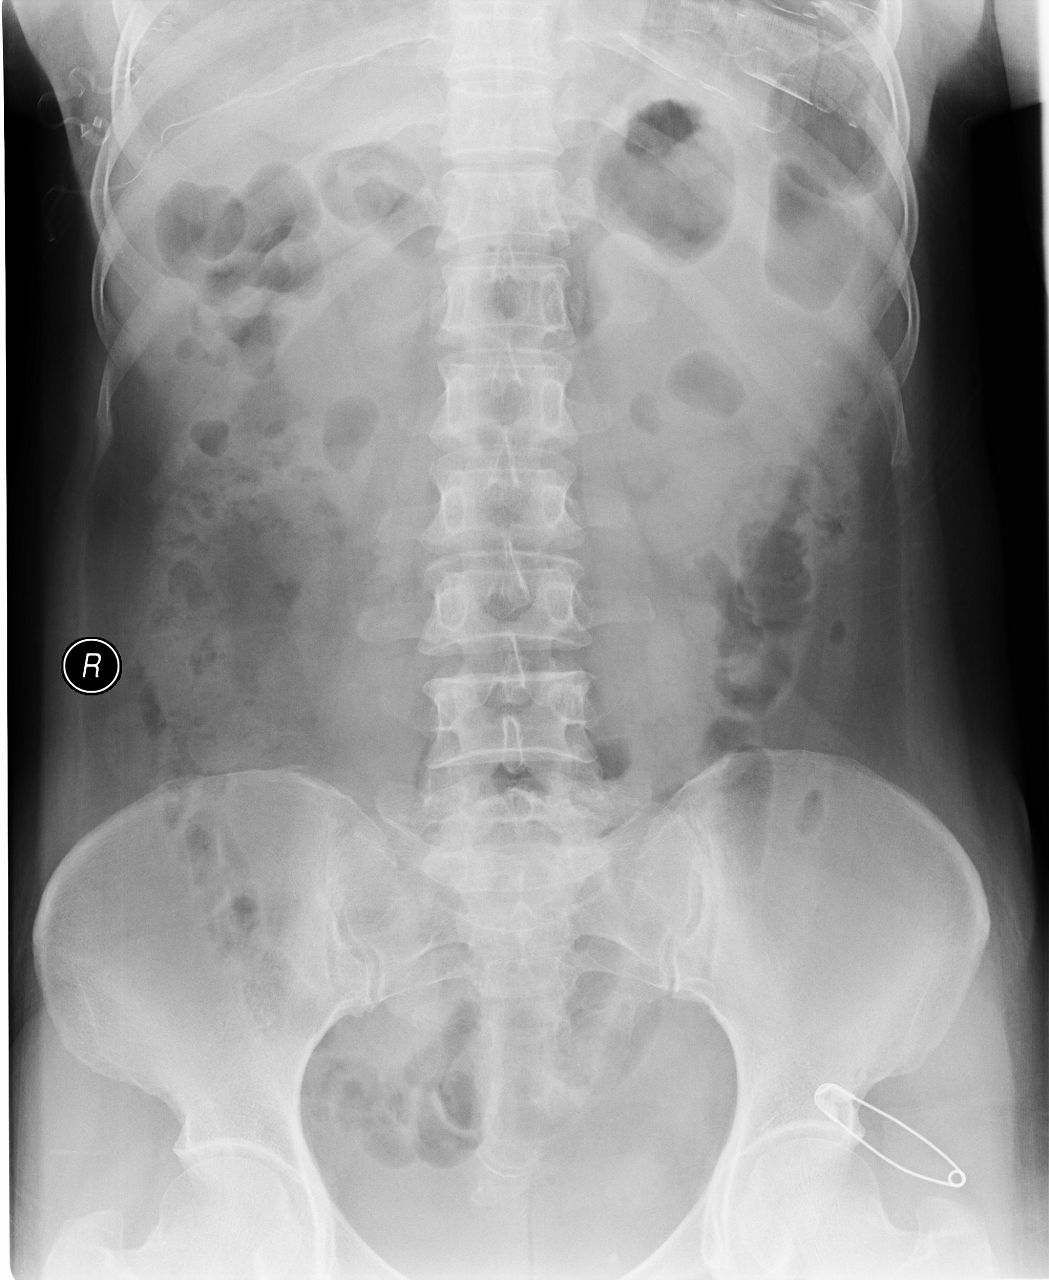

以下是引用杀毒软件在2008-7-27 17:11:00的发言:[br]肾盏分离,末端完整并少量积水-----暂支持楼主

以下是引用shiqingfa在2008-7-27 19:47:00的发言:[br]肾盏分离,末端完整并少量积水-----暂支持楼主